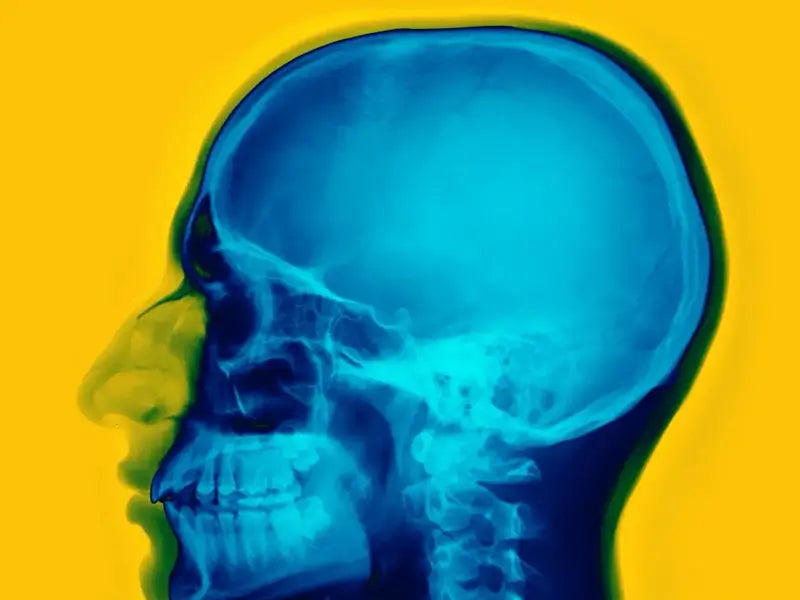

The cranial cavity (part of the human skull) creates a resonant chamber around the cochlea, influencing how we perceive sound loudness, richness, and timbre (Figure 1). These resonances vary across individuals across a frequency band that ranges from 30 Hz to 5 KHz. (Figure 2) The frequency response of each cranial cavity further anti-resonances at selected frequencies. For example, People with smaller skulls, tend to have higher fundamental skull frequencies. Cranial resonances affect how we experience certain musical elements, particularly in terms of which sounds we find unpleasant. Their interaction with other factors like neural processing of rhythm and pitch shape our behavior to music [1].